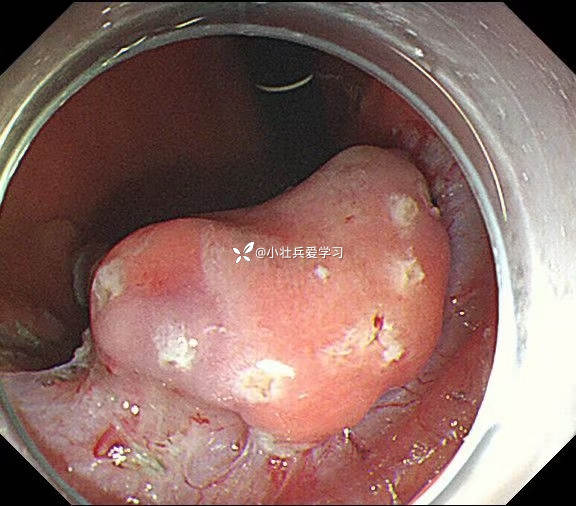

胃角早癌一例,发现一例早癌,挽救一条生命,幸福一个家庭。

临床诊断:溃疡型胃角早癌

术前谈话诊断性ESD

术后病理示粘膜内癌(M3期),切缘阴性,达到治愈性切除标准,术后不用再追加外科手术、放化疗,对病人来说是不幸中的万幸。